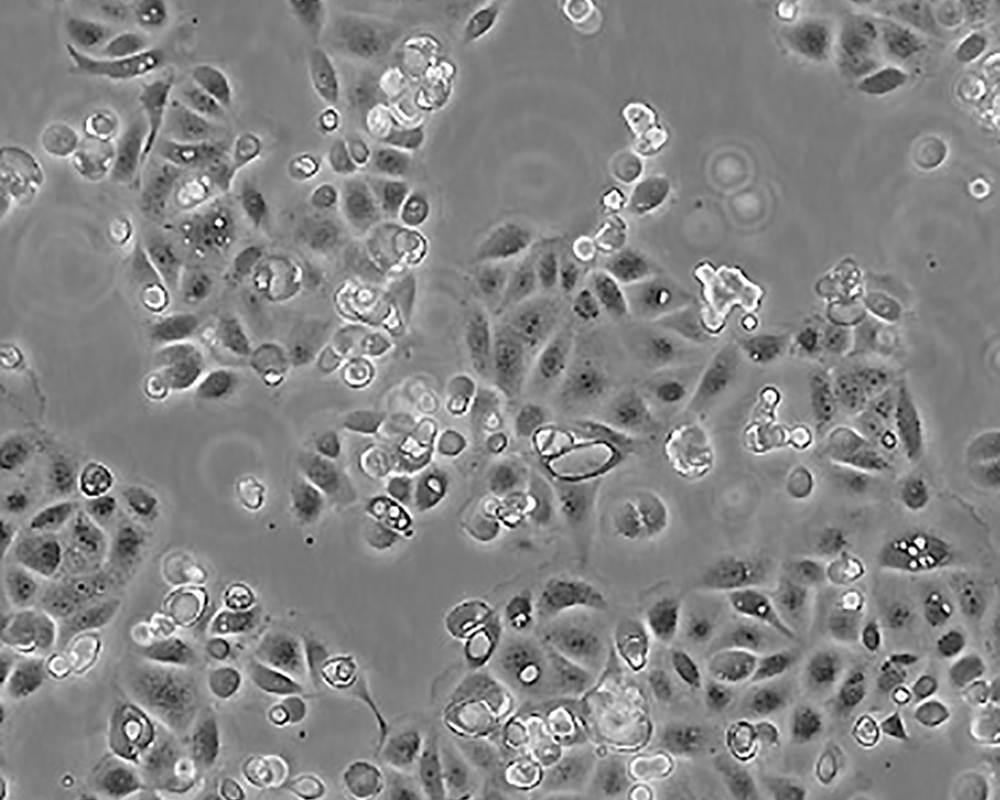

SW 1990

產(chǎn)品名稱 SW 1990

中文名稱 人胰腺癌細(xì)胞

生長(zhǎng)特性 adhere

形態(tài)特征 epithelial

細(xì)胞描述 1978年從胰腺外分泌腺的胰腺腺癌II期患者的脾轉(zhuǎn)移灶中建立了SW 1990細(xì)胞株。 報(bào)道該細(xì)胞的植板率為29%。